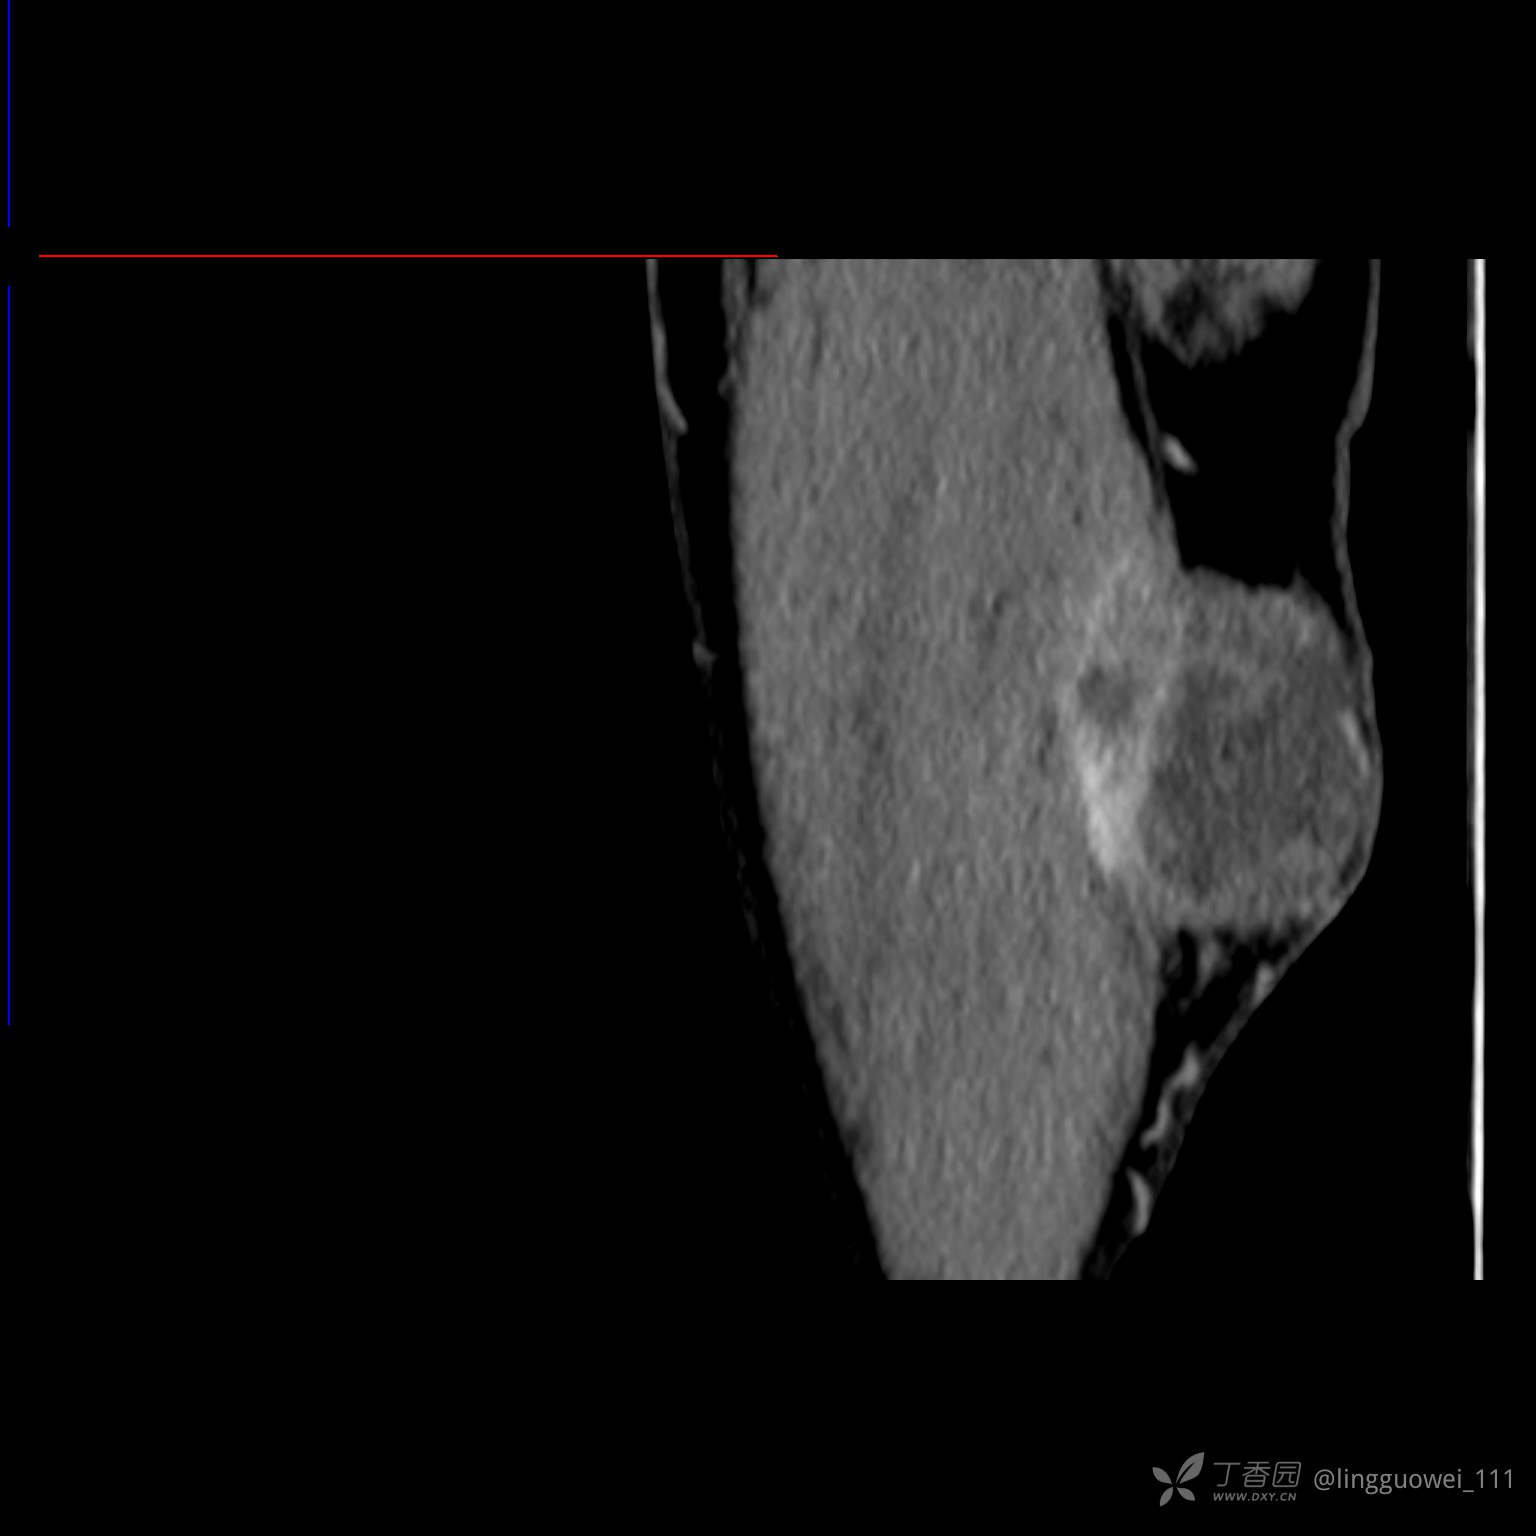

患者性别:男,85岁。发现大腿软组织肿块1年,增大3月,良性还是恶性?只有CT,能诊断正确吗?

MPR: